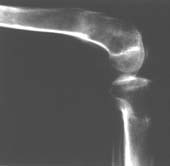

Пациент В. 53 лет, травма в феврале 2009. ДЗ. Открытый оскольчатый перелом нижней трети голени. При боли поступлении выполено ПХО, аппарат Илизарова. В последующем проводили ВХО, резекция костных отломков, укорочение 6 см, рана зажила. Была выполнена остеотомия большеберцовой кости в проксимальном отделе, резекция. Производилось тракция. На последних рентгенограммах выявлено, что одновременно с "выращиванием" регенерата произошло низведение надколенника на длину выращенного регенерата. Клинически: активное разгибание сохранено, объем движений в колене 180-110 градусов. Черными стрелками обозначен верхний край надколенника с одной и с другой стороны. Красная стрелка обозначает пальпируемую связку надколенника. Причина - остеотомия выше места прикрепления связки надколенника. Вопрос: была ли у кого подобная ситуация? Что делать? При первом обдумывании приходит решение: отсечение места прикрепления связки надколенника с костным блоком, перемещение на "правильное" место, укорочение сухожилия четырехглавой мышцы.

К сожалению, подобное осложнение "нет-нет да и возникает" при удлинении, коррекции деформации голени. В англоязычной литературе оно описано как "patella baja". Один из вариантов лечения - проксимальное перемещение надколенника приемами чрескостного остеосинтеза.